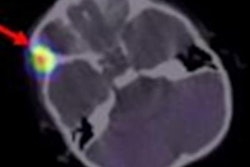

Oncologists from the Neuroblastoma and Medulloblastoma Translational Research Consortium and biomedical researchers from TGen will utilize the cloud technology to identify targeted treatments for pediatric cancer patients based on the specific genetic vulnerabilities of each child's tumor, according to Dell.